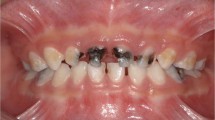

The clinical examination (CCI-2D), conducted without air-drying, included Silness and Löe's modified biofilm index;31 plaque stagnation areas (i.e., erupting molars and dental malposition); missing/absent/close-to exfoliation teeth; and teeth presenting with toothache and with untreated cavitated caries consequences (pulpal involvement, roots, sepsis [PRS]).32 Assessments at the tooth surface level (conducted after assisted toothbrushing, with the aid of a WHO probe and drying tooth surfaces and/or removing dental biofilm only with cotton rolls/gauze, without using compressed air/water) included caries severity and activity assessment using the visual epidemiological merged ICDAS (ICDAS-merged-epi) criteria: initial or non-cavitated (I); moderate (Mo); extensive/cavitated (E); and active or inactive (Fig. 1).8,26 Fillings (f/F) and missing teeth (m/M) were also registered. Teeth in need of endodontics/extraction at T0 were referred and not considered for the analyses (due to need of AGP or radiographs, restricted during the pandemic).

Table 2 shows the mean number of tooth surfaces with ICDAS-merged-epi dmfs/DMFS for the primary teeth (n = 337), permanent teeth (n = 170), and combined primary and permanent teeth (n = 337), discriminating by each dmf/DMF component and considering besides the severity and the activity status of the caries lesions. There was a significant decrease from T0 to T1y in the mean number of tooth surfaces with ICDAS-merged-epi dmfs (T0: 7.2 ± 8.9; T1y: 5.2 ± 7.1) (p <0.05) and in the ICDAS-merged-epi dmfs/DMFS (T0: 8.4 ± 9.7; T1y: 6.2 ± 7.6) (p <0.05), while without statistical significance for ICDAS-merged-epi DMF (T0: 2.5 ± 3.2; T1y: 2.1 ± 2.8) (p >0.05). With respect to caries, with the exception of DS-E and of ds/DS I+Mo+E, there were overall significant decreases in the mean number of active caries lesions, together with a significant increase in the mean number of inactive caries lesions (p <0.05). Mean number of filled tooth surfaces increased significantly (p <0.05), except for the permanent teeth.